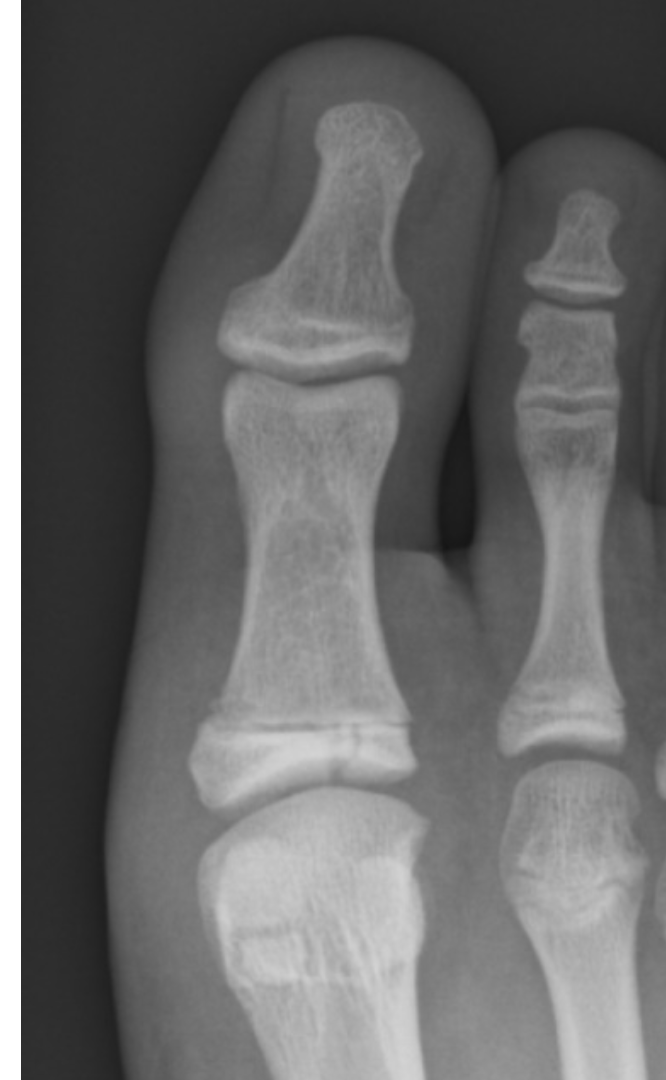

What is the main finding on the x-ray?

Salter-Harris type 1 fracture

Salter-Harris type 2 fracture

Salter-Harris type 3 fracture

Salter-Harris type 4 fracture

Salter-Harris type 5 fracture